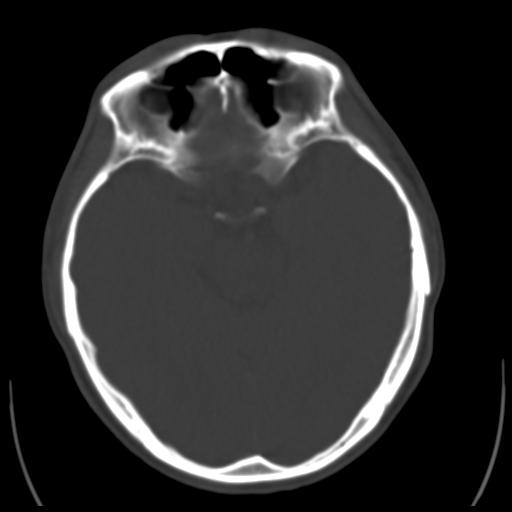

35m 鼻子时不时流血,头及右侧面部痛,颈部淋巴结未见明显大

软组织窗

这个东西大家仔细看看呀

考虑鼻咽癌侵犯颅底并突入右侧鼻腔;双侧中耳乳突炎。

建议:必要时行鼻咽镜检查(活检)进一步明确诊断。

蝶窦,后组筛窦及鼻咽部团块状软组织影,骨壁破坏,病变较广泛。考虑恶性肉芽肿。建议活检。

颅底骨质明显破坏 支持鼻咽癌 但病灶的边缘毛糙 不能除外炎性

蝶窦,后组筛窦及鼻咽部团块状软组织影,骨壁破坏,病变较广泛。考虑炎性肉芽肿性病变可能。建议活检。